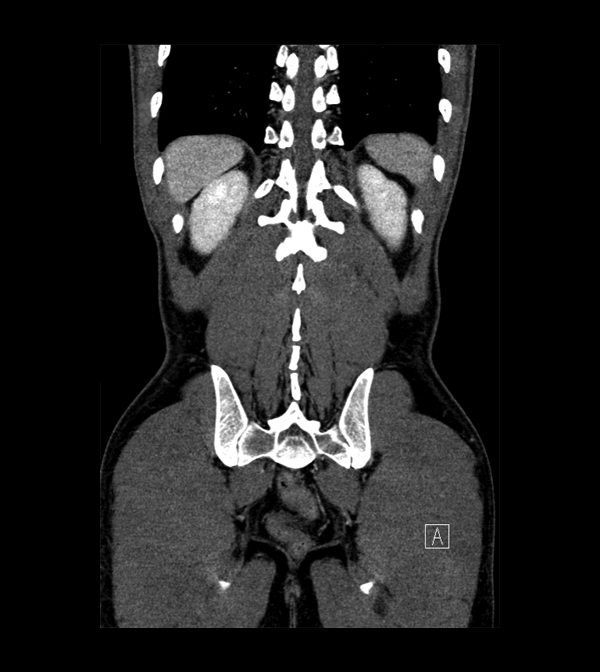

Body

Covers abdominal CT anatomy.